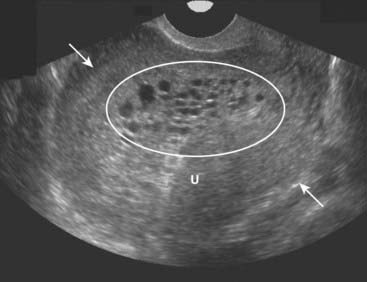

image

Figure 19-29 Molar pregnancy, sagittal view.

The uterus (U) is enlarged and filled with echogenic tissue (solid white arrows). There are innumerable, relatively uniform-sized cystic spaces that represent hydropic villi (oval) in this complete molar pregnancy. In a complete molar pregnancy, there is no fetus.